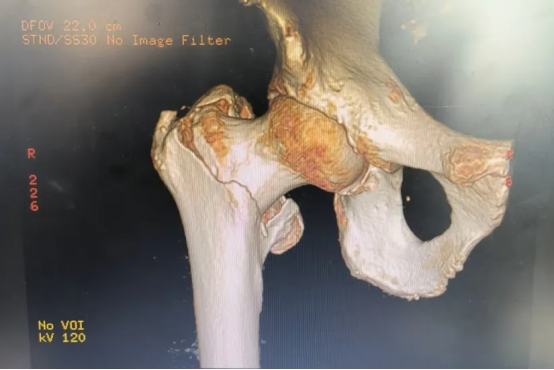

术后摄片

手术均顺利完成。术后,多学科团队开展多模式镇痛和早期康复训练,三位老人当天即可在助行器辅助下床行走。其中,95岁的夏爷爷术后6小时自主进食,12小时后开始离床训练;八十多岁的陈爷爷和王奶奶也分别于术后8小时和10小时实现下床行走。目前,三位老人恢复情况良好,正在进行后续康复治疗。